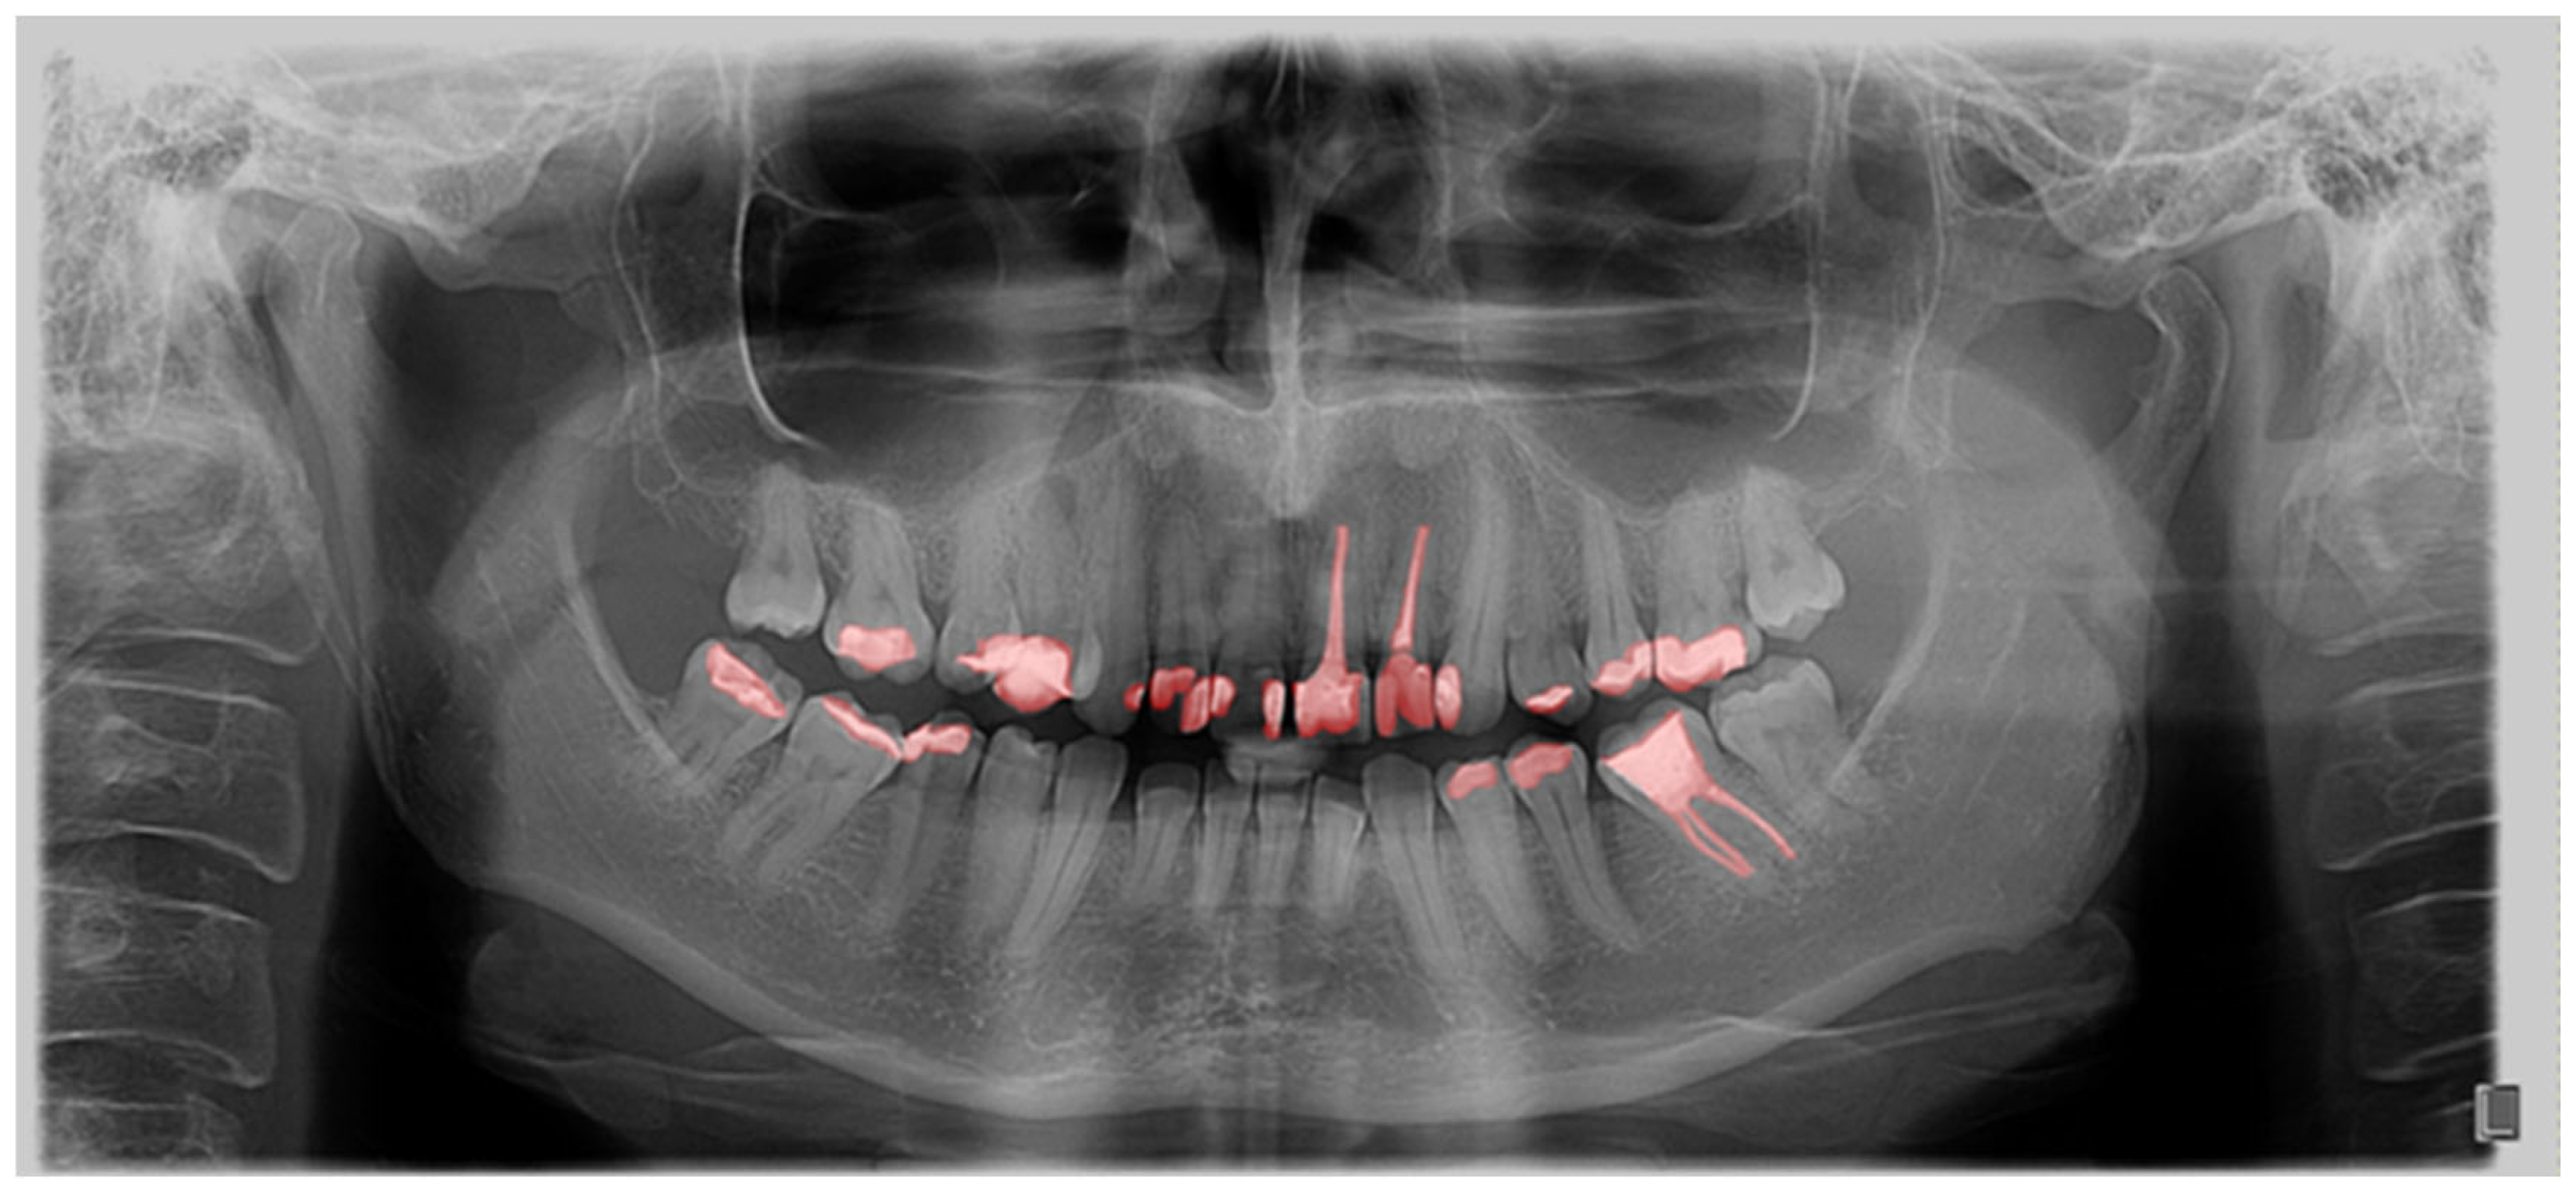

The computer program GIMP 2.10.22 was used to process the OPGs. GIMP is a powerful, free, and open-source image editor. The tool’s editing capabilities provided the annotators with a robust toolbox to adjust image parameters, helping them better discern the boundaries of the target regions. Importantly, the original OPGs were not modified during this process; everything except the annotated masks was discarded. Additionally, GIMP’s open format facilitated easy handling of per-pixel annotation data. Regarding annotation speed and validation, marking an entire tooth took about 10 min, while segmentation time depends on the number of interventions the tooth has undergone. For validation, we conducted multiple rounds of annotation-review iterations. Annotations were saved as XML files in the PASCAL VOC format for further use in neural networks. Every annotation step was conducted manually by a human expert; no annotations were automatically generated. Within the program, each tooth was outlined, covering the entire range of the tooth, including the crown and root (Figure 1). Teeth were labelled using the dual or binary system (FDI).

Figure 1. Segmentation of teeth on OPG in the GIMP program.